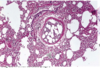

This is from a patient who had ARDS. Was this biopsy taken soon after the attack or later?

This shows hyaline membrane formation so the biopsy was likely taken soon after disease.